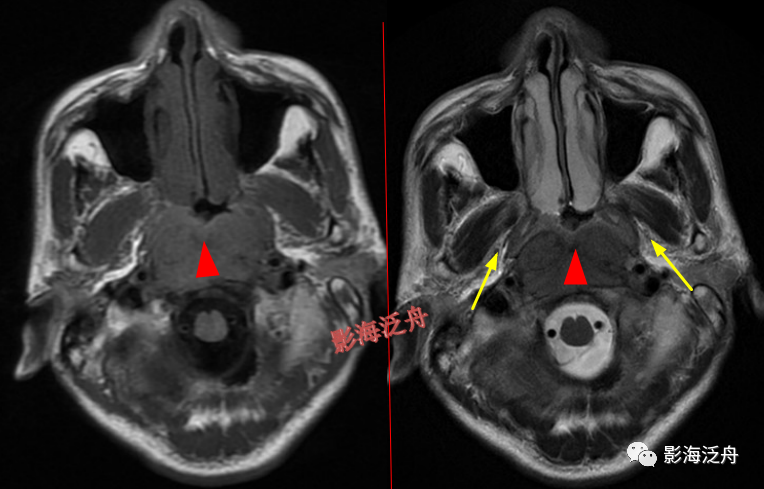

左侧岩尖部囊性病变(红箭头),患者未术,病理不明。MR对骨质结构显示不佳,因此很多读者会忽略掉颅内骨质病变的观察,很多颅内病变,如三叉神经鞘瘤、鼻咽癌

等都会造成颞骨岩部(红色标注区)骨质破坏,因此,平时应对此处多加留意。黄箭头指听神经及内耳结构。

蝶骨骨纤维异常增殖症(红箭头),病灶内部可见特征性的囊变区(黄箭)。蝶骨的病变在MR上识别起来更为困难,因为蝶骨位于颅底部,此处骨骼、肌肉、脂肪等多种组织成分混杂,导致正常情况下也看起来非常乱。不要着急,慢慢学。